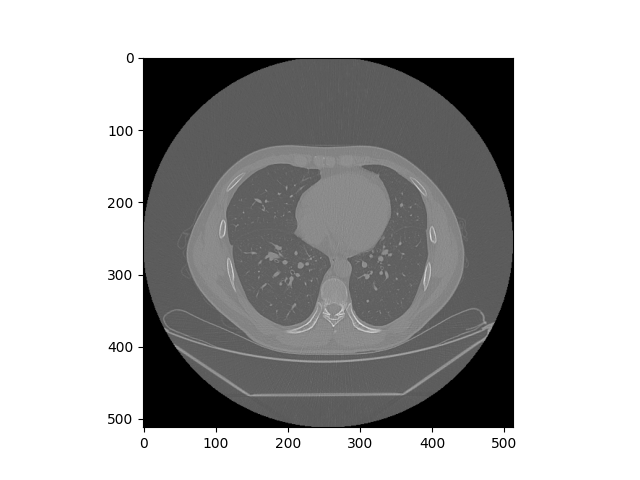

最后将图片转成的数组通过一些Hu像素的转化,使用点运算,将影像值转换为Hu值,然后通过调整vmax和vmin的属性,生成医学概念下的纵膈宽和肺部窗宽图像,对于肺部窗宽,调整之后会比之前呈现更好的亮度,而对于纵膈宽,调整之后会明显呈现一个关键部分突出的图像,如下所示

1210

图 7 肺部窗宽调整前后对比图

1110

图 8 纵膈宽调整前后对比图

121

122 ww=400

123

124 wl=40

125

126 plt.imshow(hu_ar,cmap='gray',vmin=wl-ww/2,vmax=wl+ww/2,interpolation='nearest')

127

128 plt.savefig('./tmp/11.png')

129

130 plt.show()